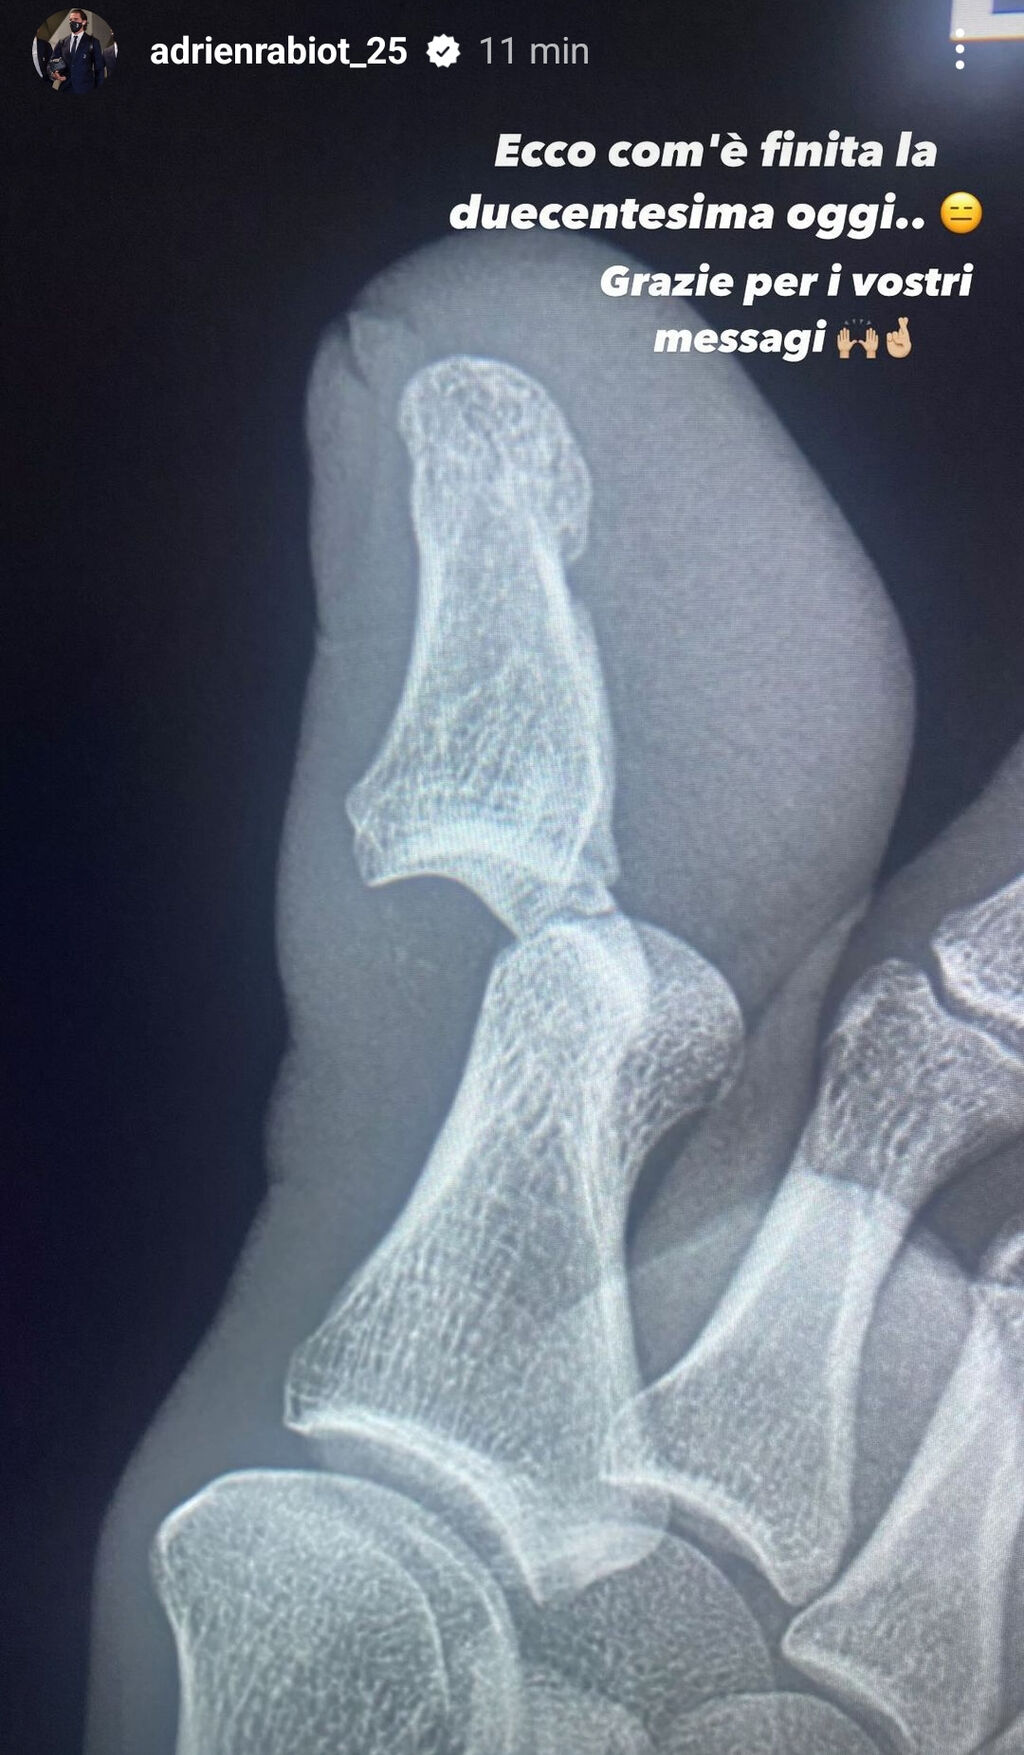

La partita di Adrien Rabiot contro il Frosinone si è interrotta per infortunio al minuto 28. Il centrocampista è uscito vistosamente zoppicante e ha lasciato il posto al giovane Alcaraz. Nelle prossime ore sono in programma i suoi esami strumentali che certificheranno l'entità del problema: stando alle ultime indiscrezioni si tratta di una lussazione alla falange dell'alluce destro. Proprio l'ex Psg ha postato una foto sui propri social della lastra effettuata al piede destro che preoccupa e non poco i tifosi bianconeri. "Ecco com'è finita la duecentesima oggi... Grazie per i vostri messaggi", le sue parole rilasciate su Instagram.